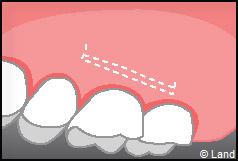

LES TECHNIQUES SANS APPORT DE GENCIVE :

Elles font appel à des lambeaux de gencive restante à proximité des récessions, qui sont déplacés et repositionnés sur la récession.